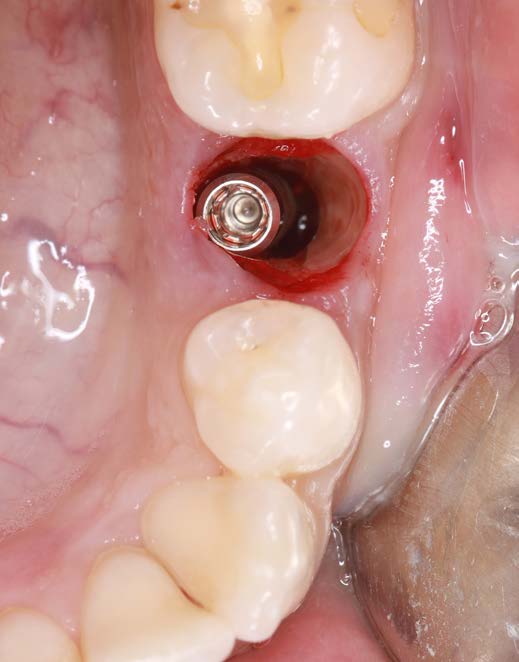

Figure 4: Condition after implantation

The Socket Shield Technique is not easy to perform. High-quality instruments are essential. Cuts must be fine and precise with minimal pressure. For this case, I used the H254LE 314 012 bone mill (Komet Dental) with a cross-cut design (right-right fluting), which runs smoothly and cuts efficiently. Its thin cut and controlled use in a red contra-angle handpiece make it ideal. I used it to section the tooth and shape the root remnant. Then, I refined the root with instruments 8831L, 831LEF, and ZR8801L (Komet Dental) - all of which allow fingertip control and effective cutting.

After osteotomy, I placed a 3.75 mm diameter implant, filled the gap between implant and root surface with allogenic bone substitute, inserted a provisional, and later restored with an aesthetic ceramic crown.